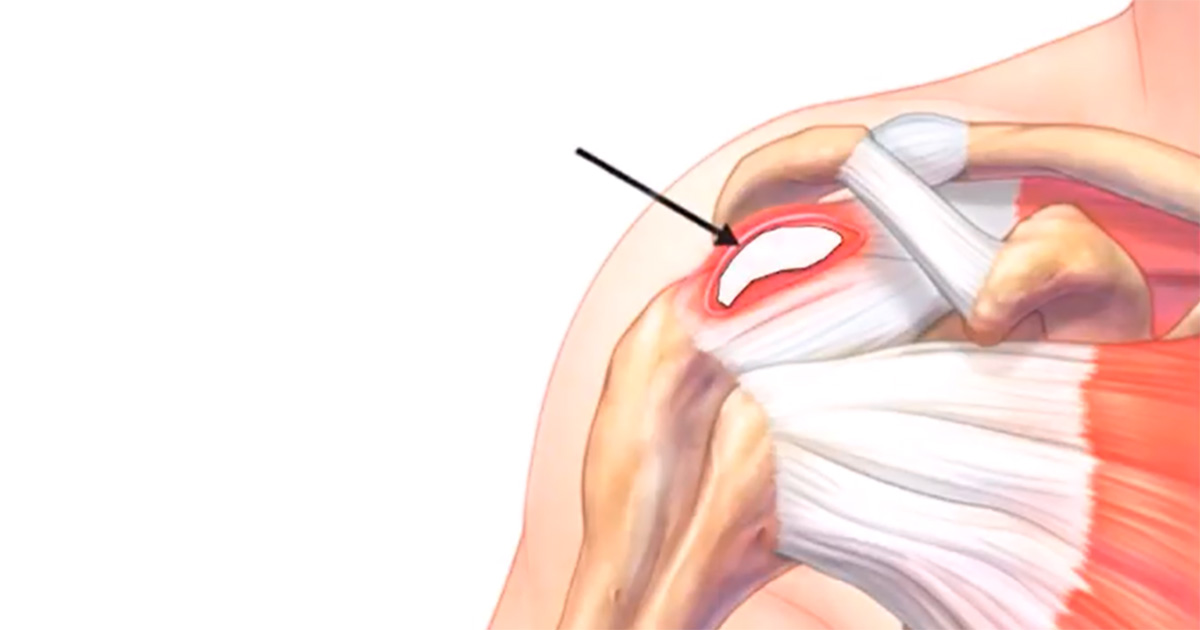

Sabe aquela dor chata no ombro que não passa de jeito nenhum? Se o diagnóstico for tendinite calcária, a cirurgia entra em cena quando os tratamentos conservadores não dão o resultado esperado. Eu falo de fisioterapia, medicação, injeções… tudo isso se esgota e a dor continua limitando seu dia a dia, é hora de pensar em outras opções. A cirurgia visa remover o depósito de cálcio que está ali, incomodando e causando a inflamação.

Existem diferentes técnicas cirúrgicas, mas o objetivo é sempre o mesmo: aliviar a pressão e permitir que o tendão se cure. Muitas vezes, o procedimento é feito de forma minimamente invasiva, por artroscopia. Isso quer dizer que o cirurgião faz pequenas incisões e usa instrumentos delicados, guiados por uma câmera. As vantagens são muitas: recuperação mais rápida, menos dor pós-operatória e cicatrizes bem pequenas. Eu mesma já vi pacientes voltarem às suas atividades em bem menos tempo do que imaginavam.

É importante lembrar que a cirurgia não é a primeira opção, mas quando ela se torna necessária, o alívio pode ser surpreendente. O tempo de recuperação varia, claro, mas a fisioterapia pós-cirúrgica é fundamental para recuperar a força e a mobilidade do seu ombro. Converse abertamente com seu médico sobre todas as suas dúvidas e expectativas. Ele é a pessoa certa para te guiar nesse processo.